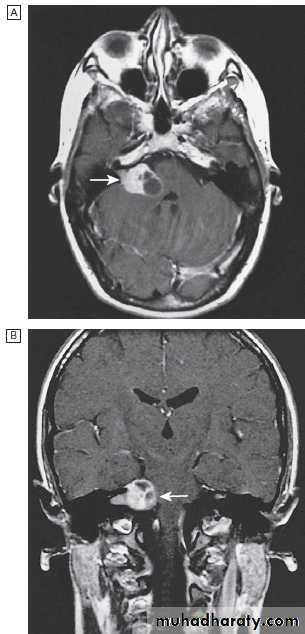

Fig. Different techniques of imaging the head and brain. A Skull X-ray showing lytic skull lesion (eosinophilic granuloma – arrow). B CT

showing complete middle cerebral artery infarct (arrows). C MRI showing widespread areas of high signal in multiple sclerosis (arrows). D SPECT after

caudate infarct showing relative hypoperfusion of overlying right cerebral cortex (arrows).